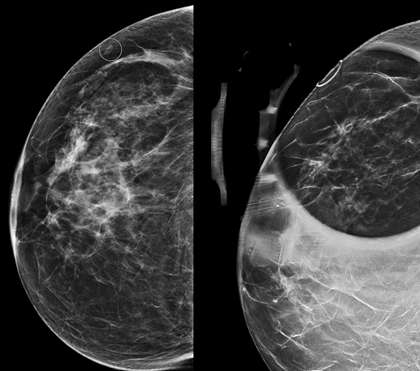

Case: Skin Lesion Figure 1

Figure 1. Mammography shows an apparent oval mass near the breast surface (left) which is then confirmed to be dermal in origin with tangential view (right). Upon direct visualization, the dermal lesion corresponds to a nevus.